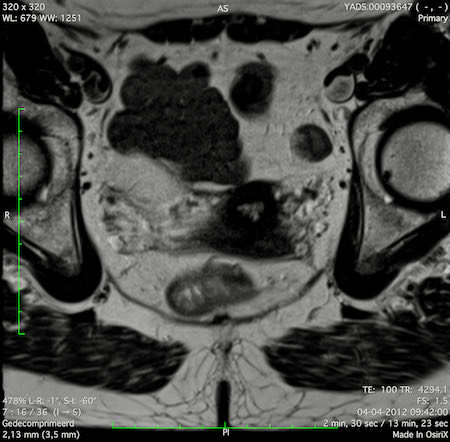

Hình ảnh

Các hình ảnh được cung cấp cho thấy ung thư biểu mô tế bào nhẫn với tình trạng dày lan tỏa thành trực tràng, hình ảnh bia bắn điển hình, và sự xâm lấn mỡ mạc treo trực tràng.